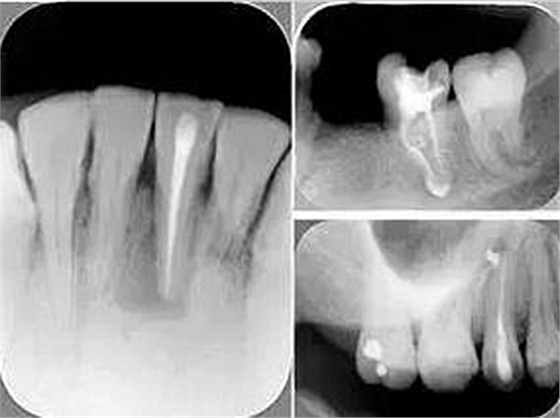

6. 術(shù)后 X 線(xiàn)片

術(shù)后 X 線(xiàn)片用來(lái)評(píng)定根管充填 長(zhǎng)度、致密度(管壁清晰、側(cè)枝)等指標(biāo)。

左圖為根管充填術(shù)后 X 線(xiàn)片。圖中可見(jiàn),根管充填較好。右下圖有白色小點(diǎn),為側(cè)方加壓導(dǎo)致糊劑擠出所致,表明根管充填比較致密。

致密、恰到好處的充填可去除干凈根管里感染灶,機(jī)體逐漸恢復(fù)。

多根牙時(shí)候需進(jìn)行偏移投照,正位投照無(wú)法說(shuō)明具體哪根牙根管充填效果。

常見(jiàn)有修復(fù)性鈣化和增齡性鈣化。下面為根管鈣化 X 線(xiàn)片。

下圖為器械折斷的 X 線(xiàn)片。箭頭處示折斷器械。